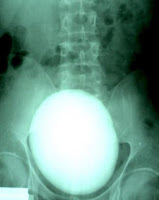

Ferva por 10 minutos e deixe esfriar. Coe, ponha em uma jarra com tampa e guarde na geladeira. Beba um copo todos os dias, e você vai perceber que o sal e outros venenos acumulados nos rins saem na urina.

A salsa contém também ferro (5.5mg /100g), manganésio (2.7mg / 100g), cálcio (245mg / 100g) e potássio (1mg / 100g). É recomendada para pedra nos rins, reumatismo e cólica menstrual. Sua alta concentração de vitamina C ajuda na absorção de ferro. O suco de salsa, sendo uma bebida natural, pode ser tomado misturado com outros sucos, 3 vezes ao dia. As folhas podem ser mantidas no congelador, e seu uso é recomendo na culinária diária, pois além de saudáveis, dão ótimo sabor a qualquer receita. Ótima dica para hipertensos!